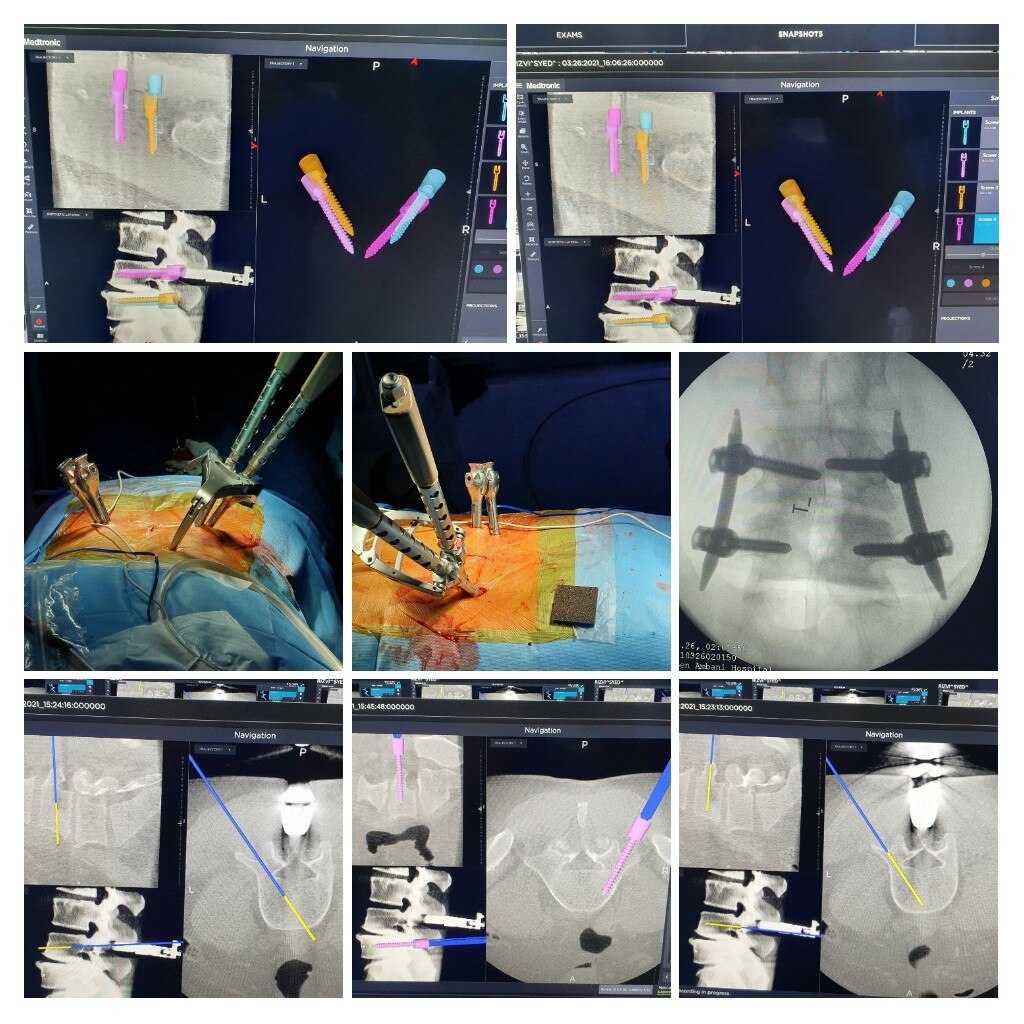

Dr Abhijit Pawar is the Best Spine Surgeon in Pune. He is the leading Minimally Invasive Spine Surgeon, Endoscopic and Spinal Deformity Surgeon, Back Pain/Neck Pain Specialist, Spine Specialist, Spine Doctor, Spine Surgeon in Baner, Balewadi, Mahalunge, Sus, Pashan and Pune. Dr Abhijit Pawar is a Senior Spine Surgeon also practices at Kokilaben Dhirubhai Ambani Hospital Mumbai(KDAH). He specializes in minimally invasive spine surgery, endoscopic spine surgery and scoliosis surgery. He is the pioneer of 3d Navigation guided (O-Arm) spine and scoliosis surgery in India. He has done extensive research in the field of spine surgery and published about 25 articles and book chapters in international spine journals. Till date he has successfully performed about 3500 successful spine surgeries at KDAH. Dr Pawar is an avid trekker and marathoner and has successfully scaled several peaks in India in the last 5 years. He is an active member of rotary club of Mumbai. With the association of rotary club and KDAH they treat needy children with scoliosis at affordable costs.